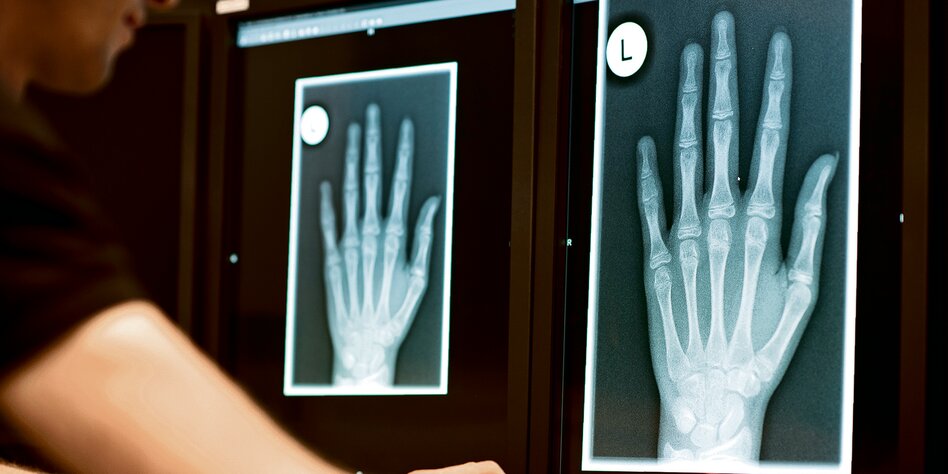

IMG Bild: Wird zur Altersfeststellung durchgeführt: Röntgenbild der Hand wie hier in Friedrichshafen